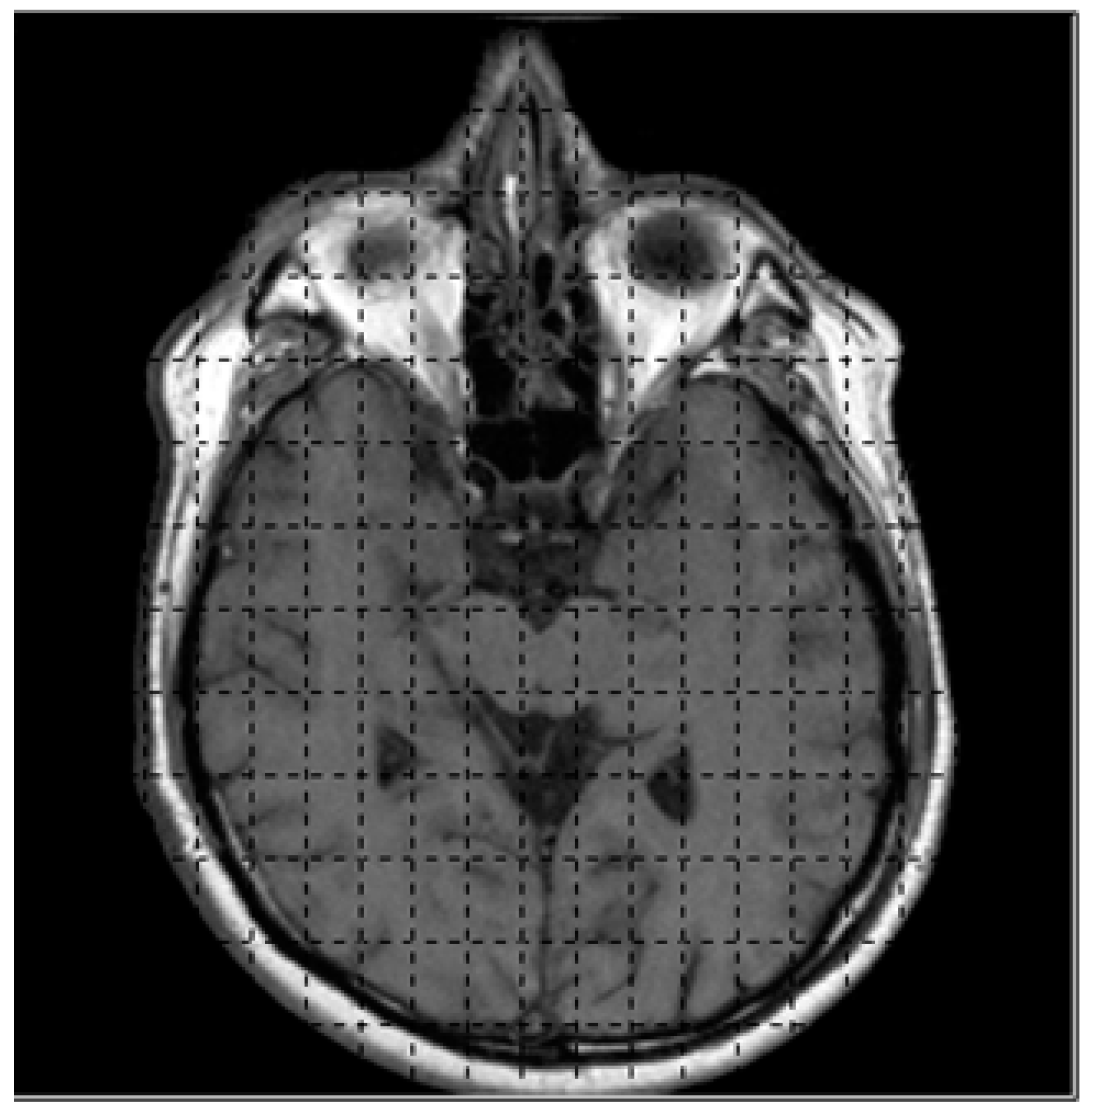

3. Reading the Intensity Value of CT Images for 3D Rendering

6. Results